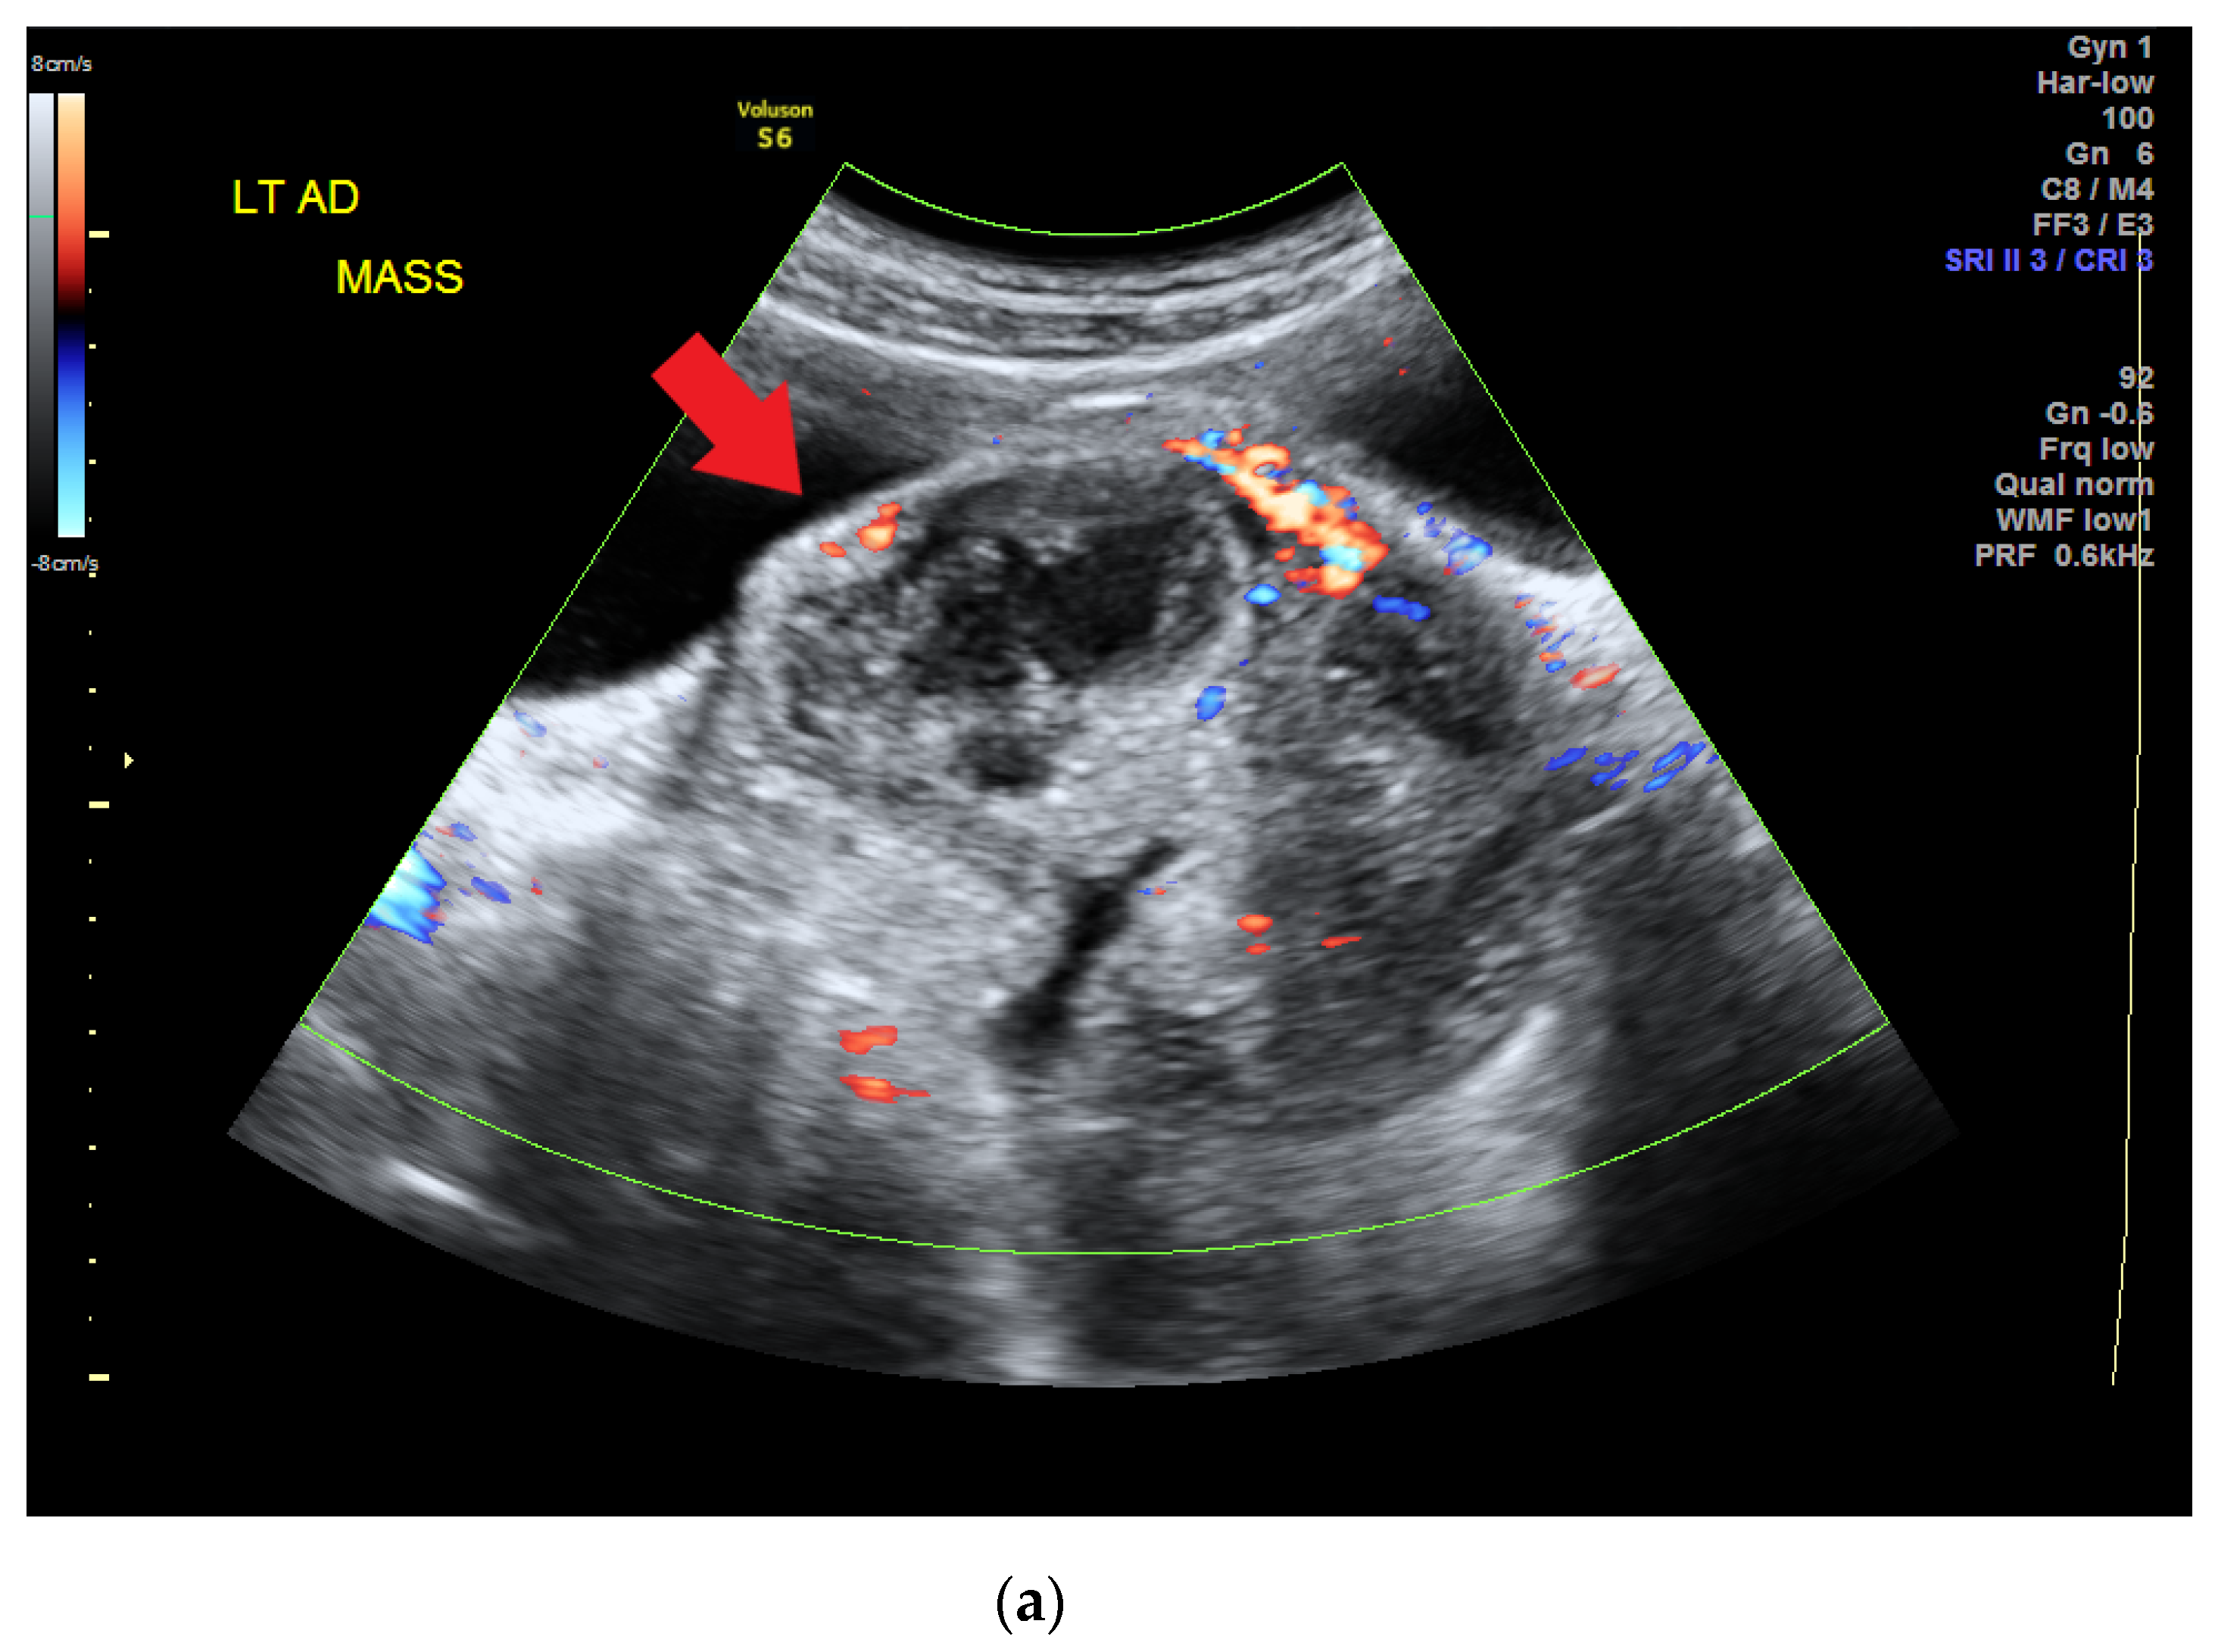

| 14 years old | Prolonged menstrual period of up to 1 month | CA-125, 77.96 unit/mL; CA-199, 57.01 unit/mL; alpha fetal protein, 94.88 ng/mL Serum albumin: 2.2 g/dL, cholesterol: 183 mg/dL, triglyceride: 133 mg/dL | CT scan: a lobulated mass lesion, maximum diameter: 10.1 cm | Malignant mixed germ cell tumor: 75% dysgerminoma, 10% immature teratoma, 10% embryonal carcinoma, and 5% yolk sac tumor | cytoreductive left salpingo-oophorectomy |